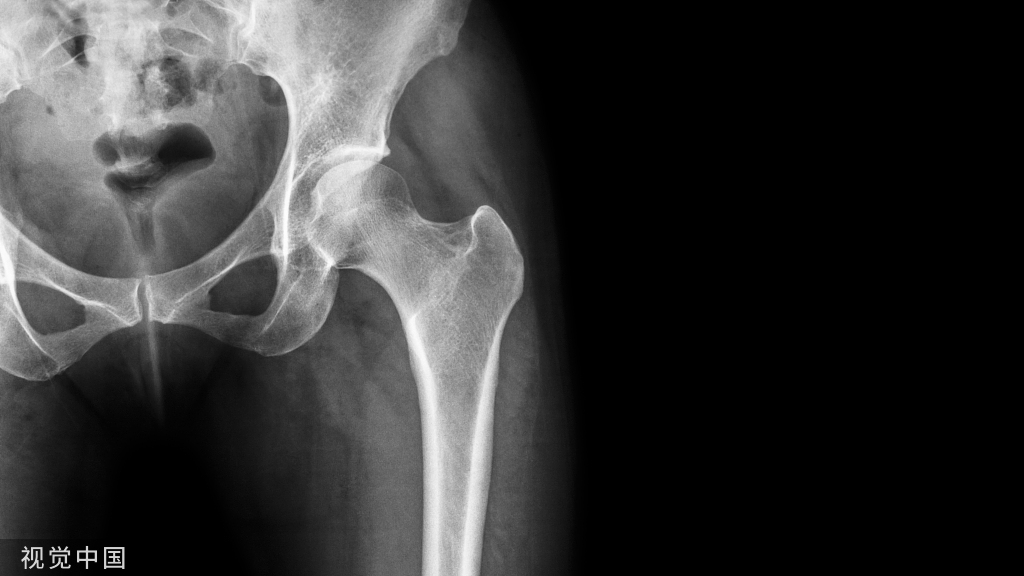

骨质疏松实验室诊断及影响因素专家共识 2022

本研 究 以《原发性骨质疏松症诊疗指南( 2017) 》为依据[1],研讨骨质疏松实验室诊断技术项目、骨质疏松诊断与鉴别诊断、实验室诊断影响因素,旨在促进骨质疏松实验室诊断技术的推广应用。本研究的主要参考文献见表 1。

《原发性骨质疏松症诊疗指南》论述了骨质疏松诊断、鉴别诊断、实验室检查,并指出在诊断原发性骨质疏松症之前,一定要重视和排除其他影响骨代谢的疾病,可酌情选择实验室检测项目,对此进行进一步的鉴别。